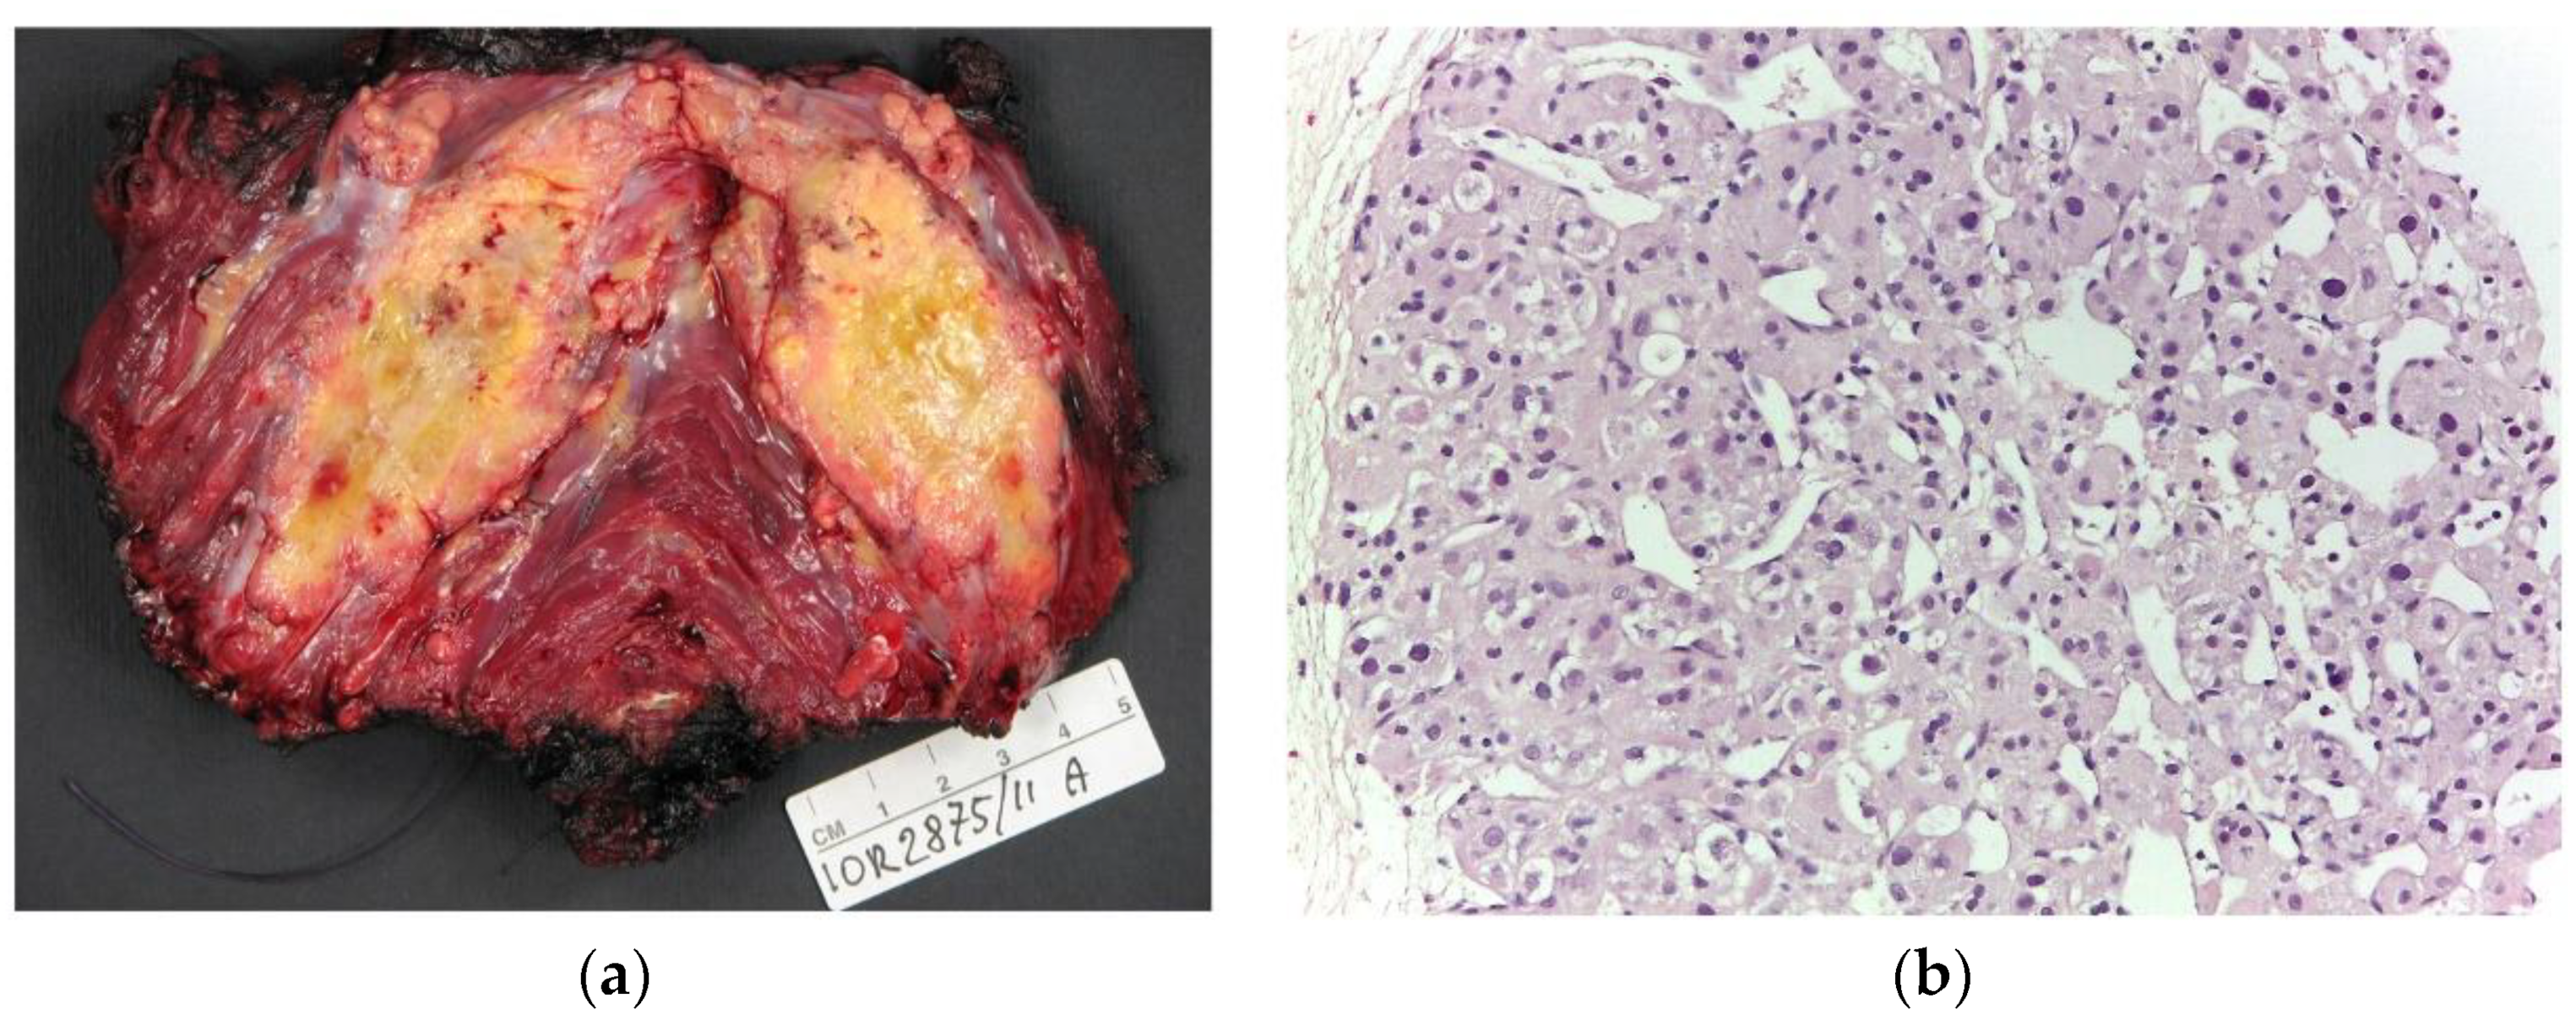

1.2. Anatomical Pathology and Genetic and Molecular Patterns

3.3. Ultrasound Features

3.4. MRI Features